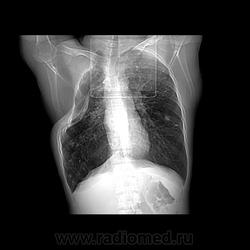

Состояние после торакопластики.

Молодой человек 30 лет, в 04 году выявлен фиброзно-кавернозный ТБ, в течение 12 месяцев лечился в стационаре, прооперирован-5реберная торакопластика справа, через 3 года переведен в 3ГДУ, в 10году снят с ДУ по излечению. Пришел провериться по ухудшению состояния. На КТ легких данных за рецидив ТБ, вроде нет. С " торакопластикой" был единственным пациентом на учете.

Состояние после правосторонней 5-реберной торакопластики по поводу ФКТ.Грубые остаточные изменения:поликистоз,буллезно-дистрофические изменения,плевропневмоцирроз правого легкого..Нет ли  мелкоочаговой диссеминации в обоих легких?Нужен Rархив.(ПТД).